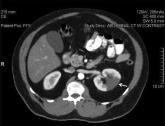

ArticleAcute Pancreatitis with Eruptive XanthomasAuthor:Fadi Makdsi, MDPublish date: January 26, 2010Read More